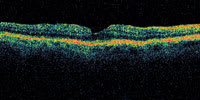

Figure 1. OCT showing early macular hole formation. The lateral separation is less than 50 μm. |

A central clinical challenge has been accurately diagnosing early macular holes which may be mimicked by many other conditions.34,35 No imaging modality has enhanced our diagnostic capability more than the OCT; superior imaging capabilities have improved diagnostic accuracy, clinical monitoring, and postoperative assessment.36-38 The OCT unequivocally demonstrates early stages of full-thickness macular holes (Figure 1), and allows distinction of pseudohole and pre-macular hole conditions in almost all instances. Fluid accumulation in early, presumed pre-macular hole stages have been corroborated by OCT observations (Figure 2). Serial images have been reported showing the progression from apparent impending macular holes to full thickness macular holes.39-42 It has depicted many other configurations that might be in the spectrum of lamellar or pre-macular hole conditions (Figure 3 and 4).